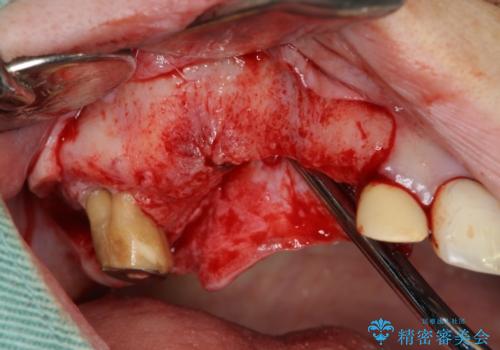

- 他院で1本インプラントを入れたまま治療に通うことができなくなり、途中からの治療を希望され来院されました。

既に埋入されているインプラントは位置が悪いのでそのまま骨内に留置することとし、新たに咬合機能を回復すべく3本のインプラントを埋入すると同時に吸収した骨幅を増やし、安定してインプラントで噛める環境整備を目指します。